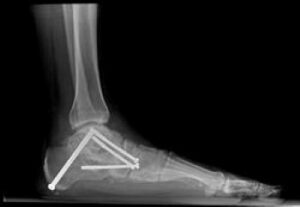

Arthrodesis (Joint Fusion)

In some cases, flatfoot is accompanied by stiffness or arthritis in critical foot joints, making traditional treatments like bone cuts and tendon transfers ineffective. Joint fusion (arthrodesis) is a surgical option to realign the foot and alleviate arthritis-related pain.- What Does Arthrodesis Involve? The procedure involves removing cartilage from the affected joint and securing the bones in a corrected alignment using screws or plates. Over time, the bones fuse to form a single, solid structure, eliminating the joint and associated arthritis pain.

- Application in Flatfoot Surgery:

- In rigid flatfoot, the heel bone may need to be repositioned and fused beneath the ankle bone.

- To restore the arch, bones along the inner side of the foot may also require fusion.

- Benefits and Motion Impact: While fusion eliminates movement in the fused joints, patients with rigid deformities typically have little to no motion in these joints before surgery. This procedure can improve walking mechanics and reduce pain, particularly on the outer ankle, by addressing arthritis and impingement between the heel and ankle. Importantly, the ankle's up-and-down motion is generally unaffected.

- Risks: A potential complication of arthrodesis is nonunion, where the bones fail to fuse together. If this occurs, a second surgery may be required.

This X-ray shows a very stiff flatfoot deformity. A fusion of the three joints in the back of the foot is required and can successfully recreate the arch and allow restoration of function.